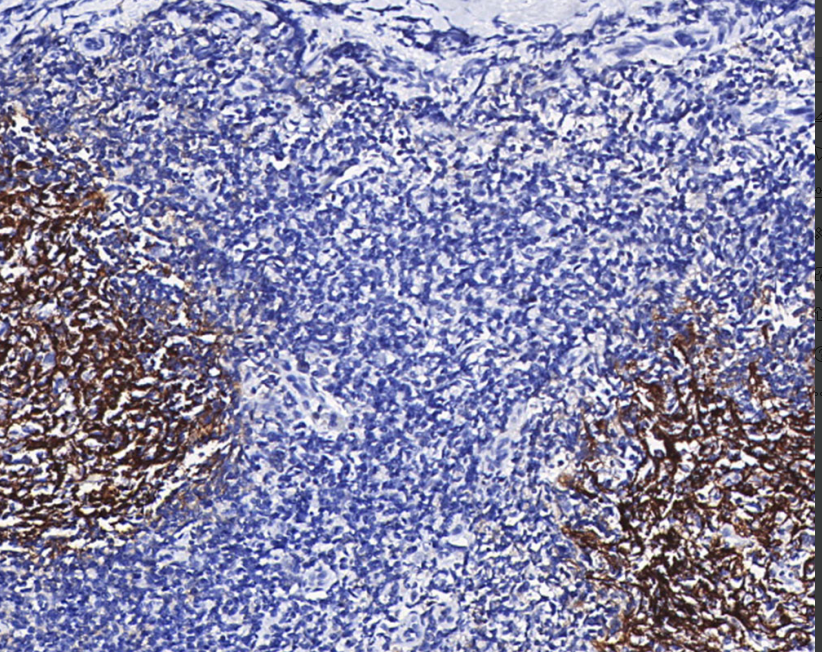

Positive control: tonsils

CD35 is a membrane-penetrating glycoprotein with a molecular weight of 210 to 220 kD that binds to complement C3b and C4b, so it is also known as the complement receptor.1 CD35 is expressed on all CD20+ B lymphocytes, CD14+ monocytes, and neutrophils, and in certain subsets of T cells (~5%).

CD35 Antibody Reagent binds specifically to the CD35 molecular antigen. Immunohistochemistry kits containing CD35 Antibody Reagent are suitable for the precise diagnosis of follicular dendritic cells and their tumors.